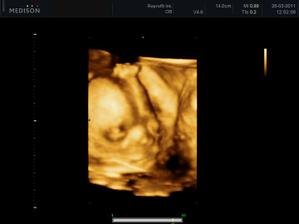

15.7.2011 - utz, malá váží 2630 g (37 tt), viděli jsme obličejík, celej táta a jsme v pořádku